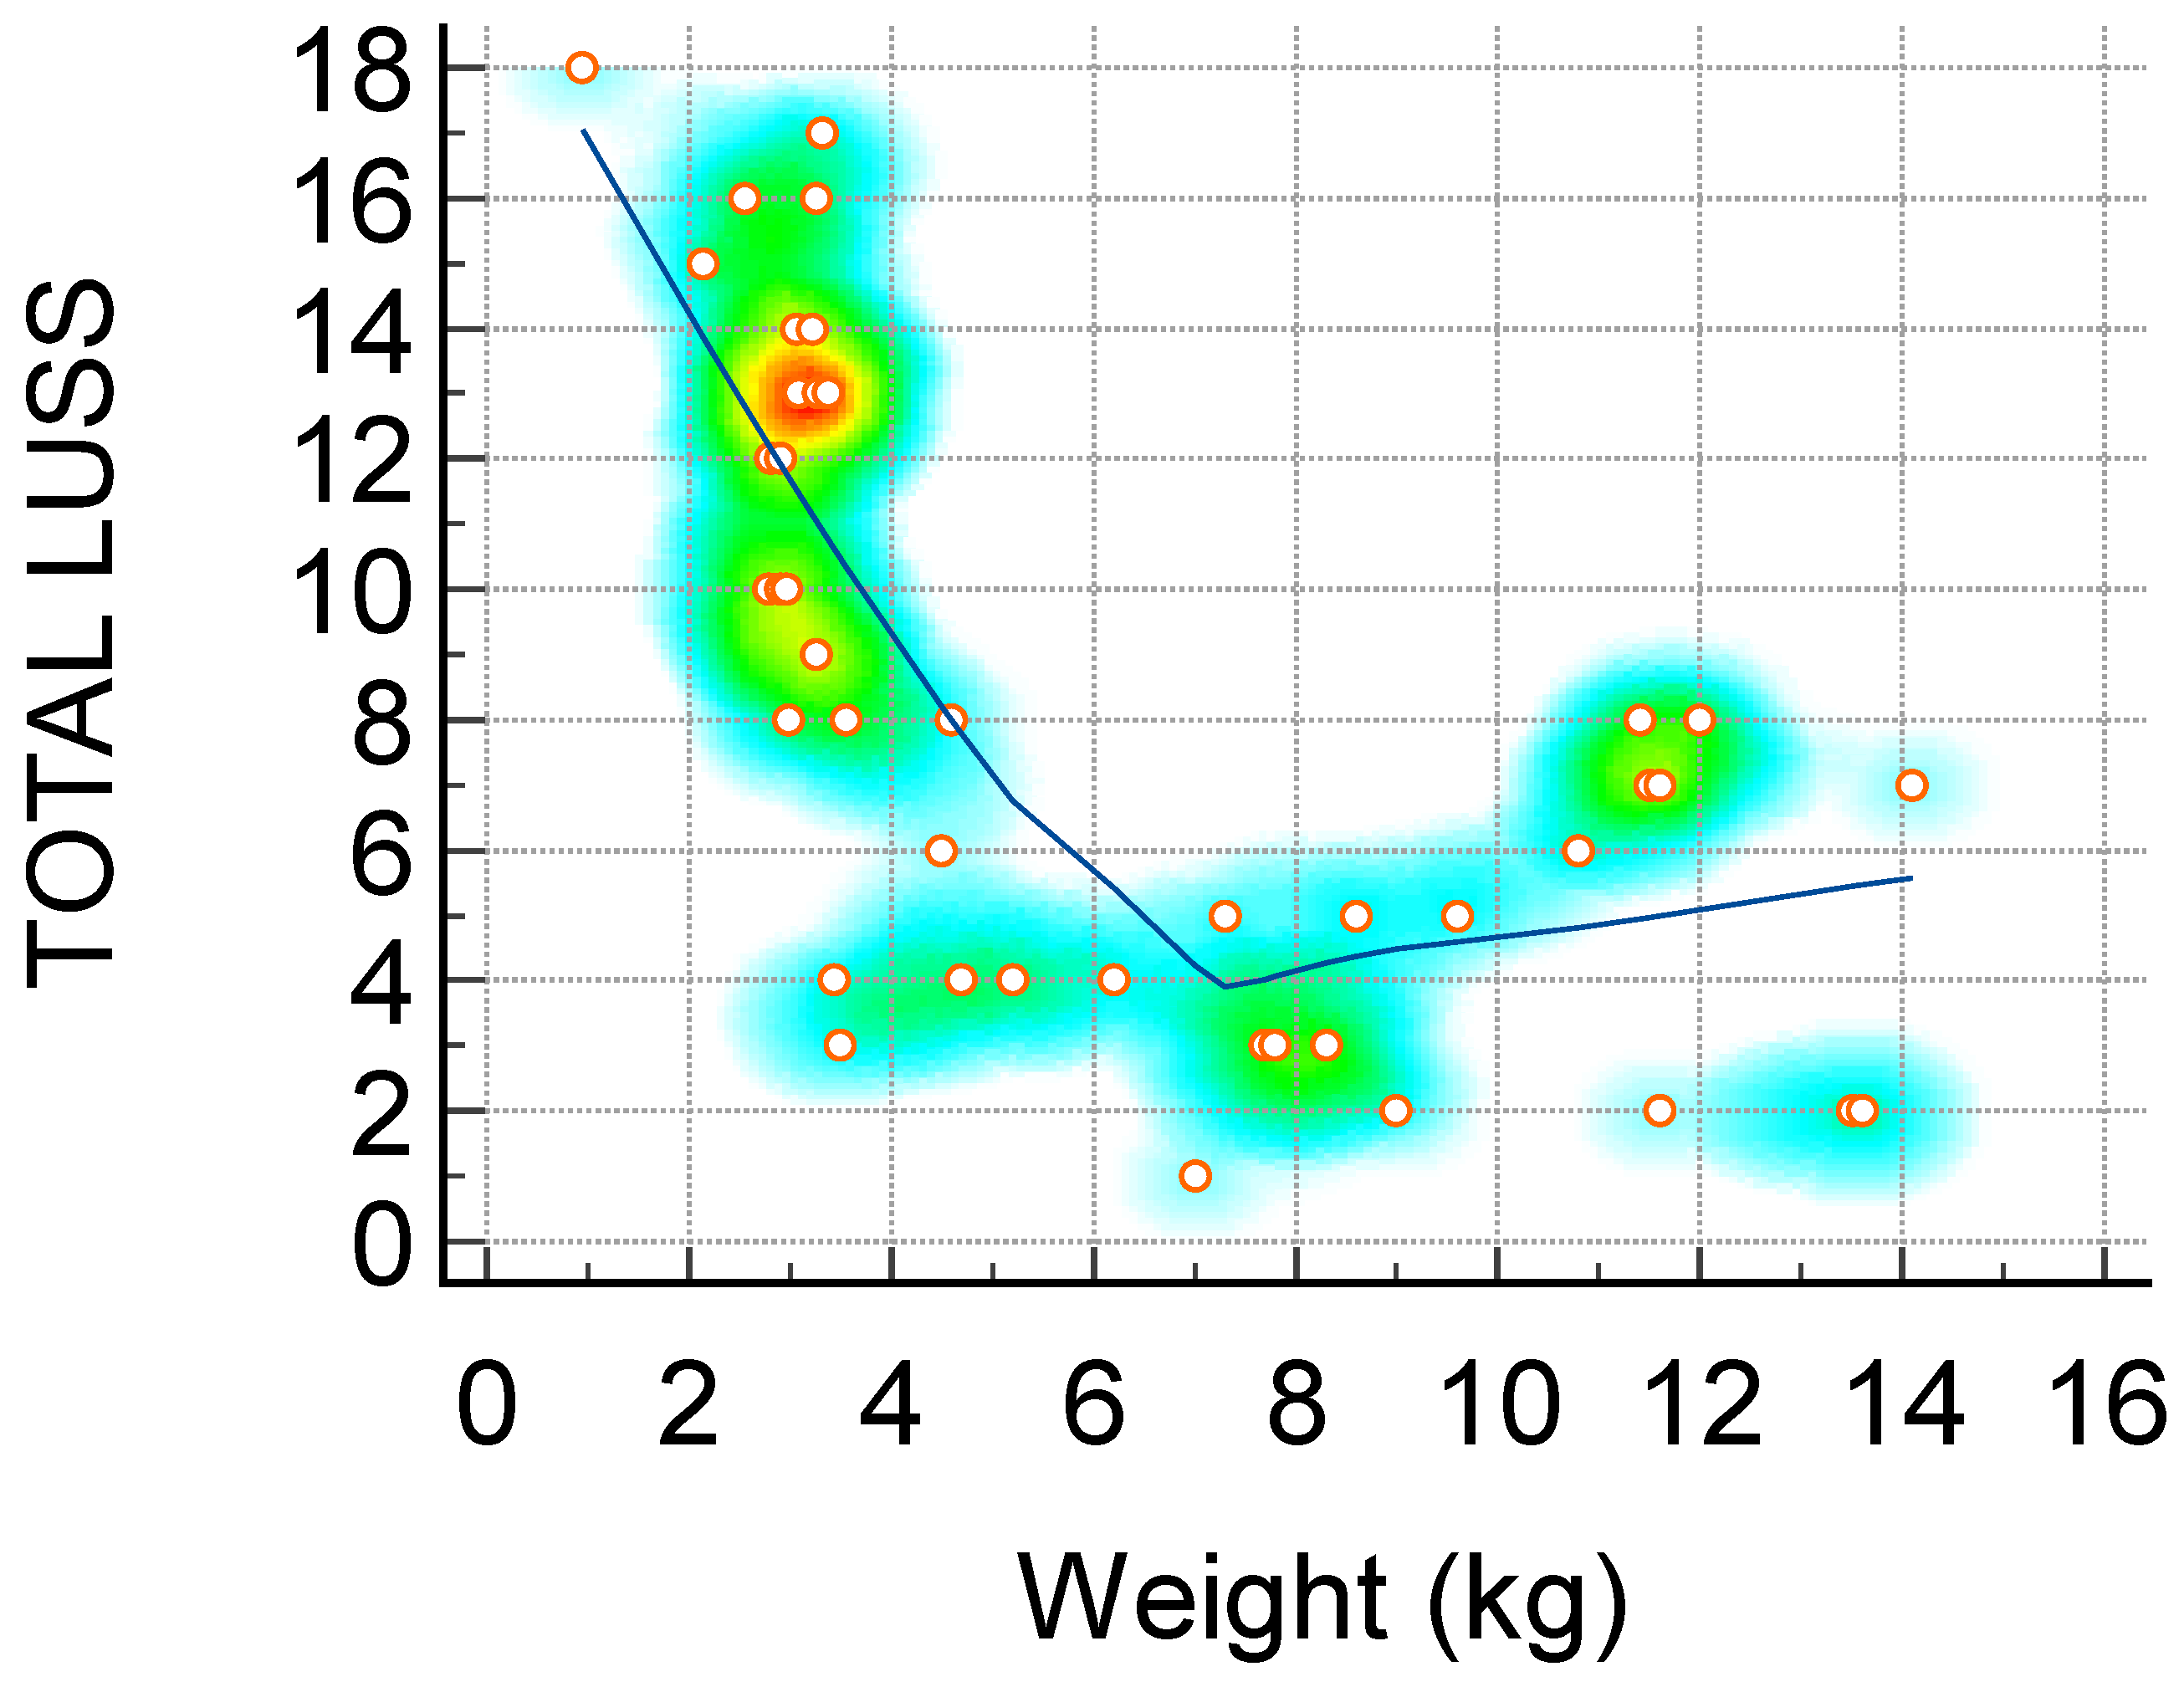

| Weight (kg)—Figure 1 | −0.72 | −0.84 to −0.53 | <0.0001 |

3.4. Lung Ultrasound Score and Correlation with Inflammatory Markers